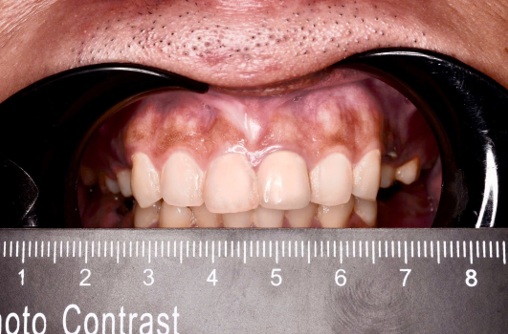

Hình 1: Hình ảnh nhiễm sắc nướu ở vùng nướu răng hàm trên

Nhiễm sắc nướu (Gingival pigmentation) là tình trạng nướu bị đổi màu, thường là do sự tích tụ của các sắc tố melanin (yếu tố nội sinh) hoặc các chất khác từ bên ngoài (yếu tố ngoại sinh).